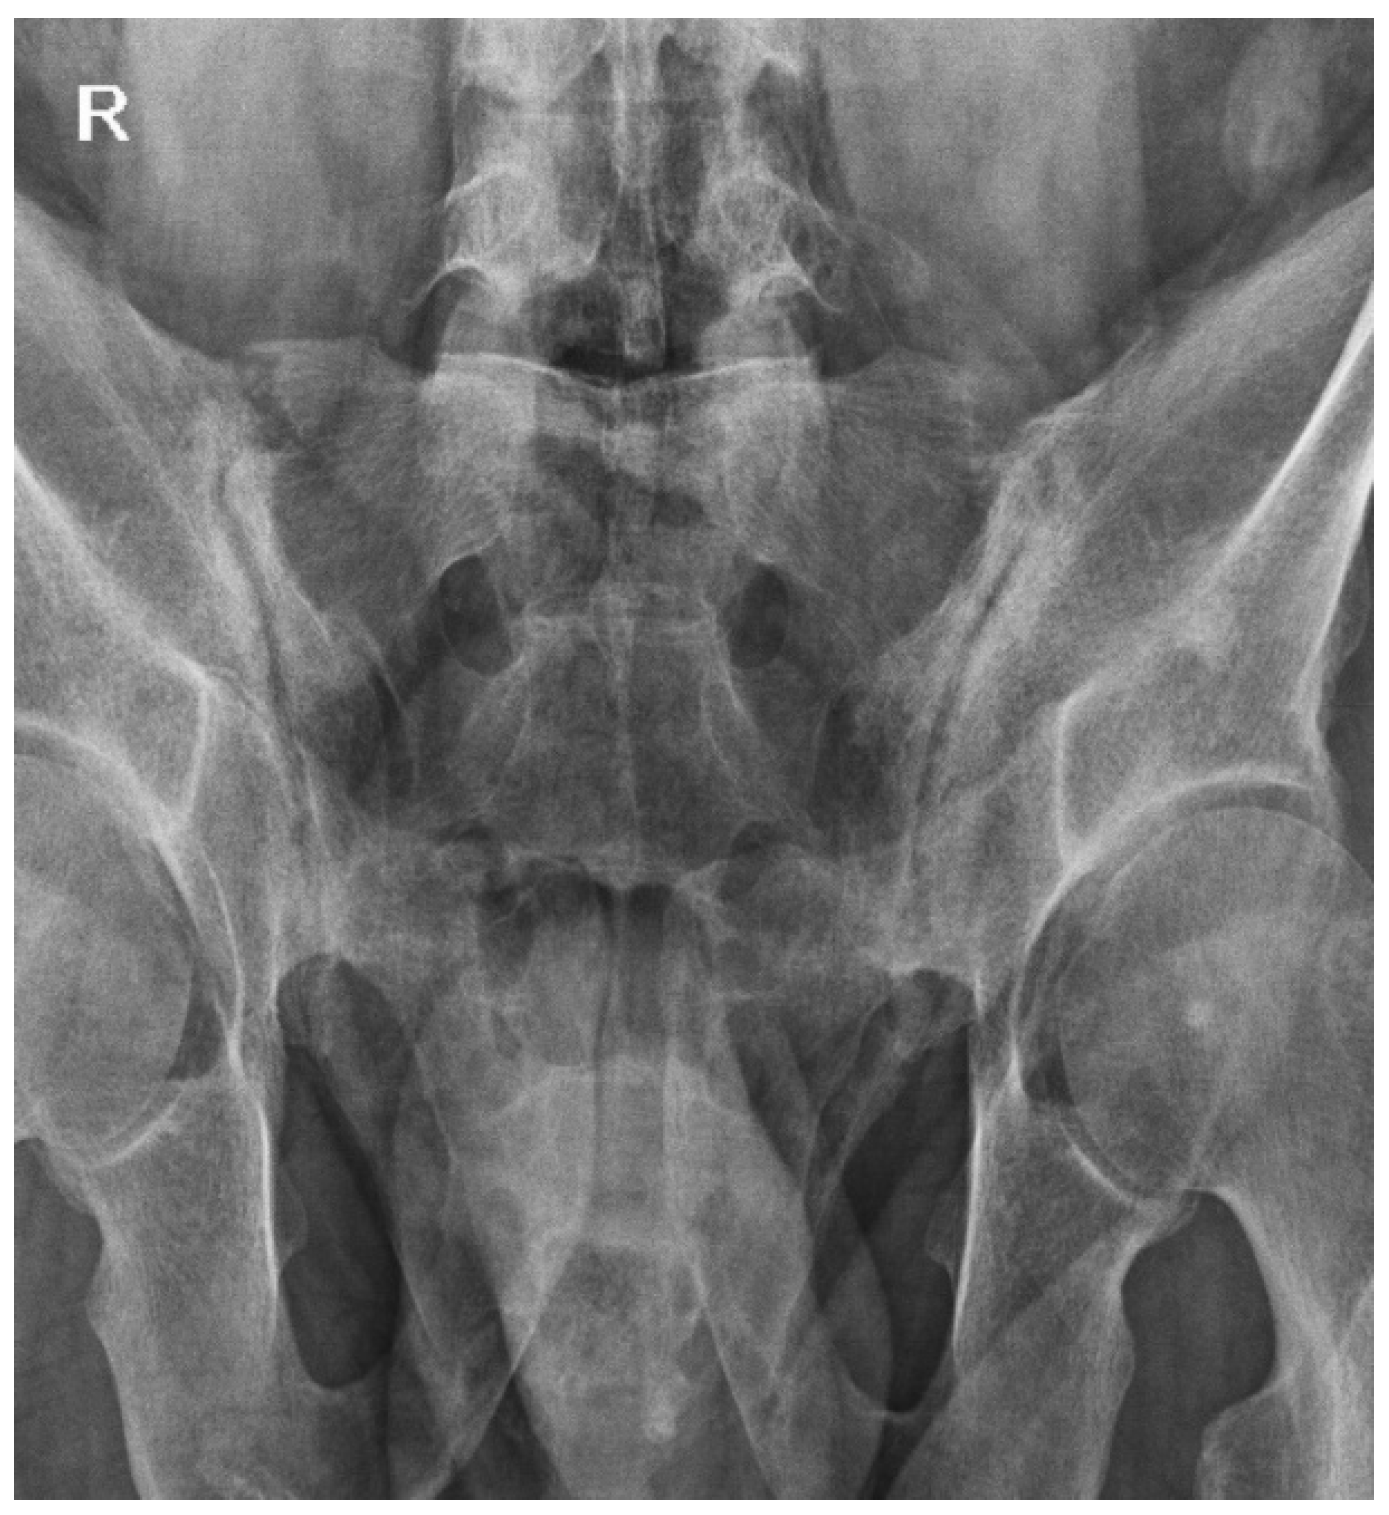

2.2. Progression and Diagnosis of Non-Radiographic Axial Spondylarthritis (2020)

2.3. Clinical Deterioration and Persistent Symptoms (June 2023)

2.4. October 2023